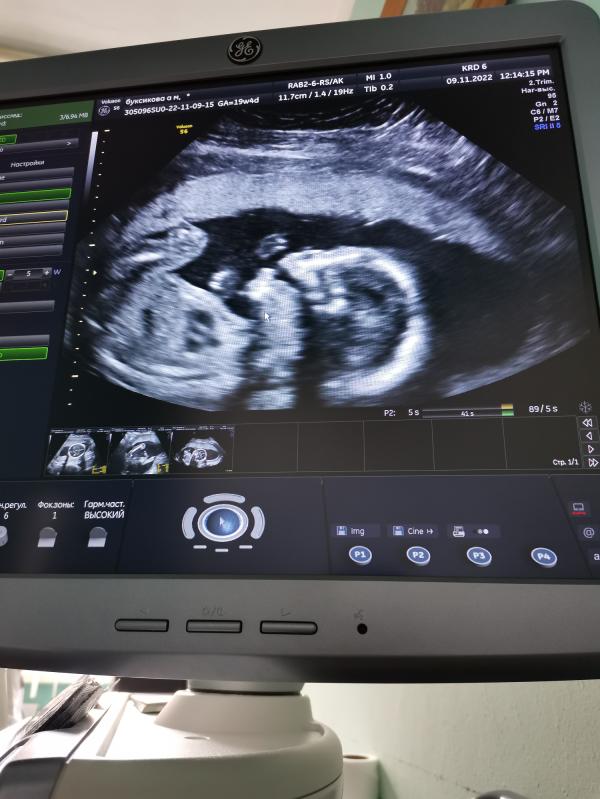

Сегодня ровно половина срока. Даже не верится, что во мне живёт этот малец😅 такой забавный, на УЗИ рот открывал)